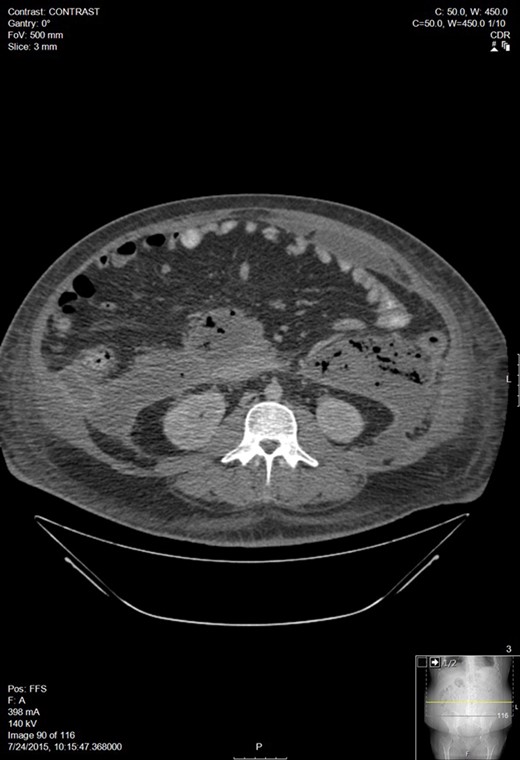

A week later, he presented to his PCP for follow up and was febrile with increasing abdominal pain. CT of the abdomen and pelvis showed an 11 Ă— 15 cm2 pancreatic fluid collection. His hemoglobin was 6.9 and he was transfused 3 units of PRBC. After transfer to our facility, a repeat CT showed a small pericardial and left pleural effusions, large volume ascites, a pancreatic fluid collection within the lesser sac between the anterior pancreas and posterior gastric body measuring 14 Ă— 16.1 Ă— 16.2 cm3, and blood in both paracolic gutters and pararenal spaces (Fig. 2). He was referred to Interventional Radiology for drain placement. After drainage, he clinically improved and was discharged.

Worsening walled off pancreatic necrosis with extension to the paracolic gutters.